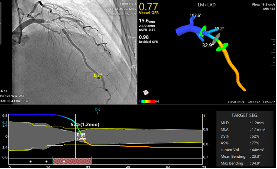

然而,患者是否需要手术、如何进行手术,严重依赖着临床医生的经验与能力。通过AI助力,前述AI-QFR系统仅需1幅造影、1步计算、1分钟内可自动完成各主干与支干河流的“河道”、“水流量”评估,诊断精确度达93%,并为介入手术提供模拟导航及术后评估。

他进一步解释称,一般来说,临床医生会对疑似冠心病患者开具造影检测,相关造影数据输入系统后,进行QFR分析,一分钟后更高清的“河道”及各“河道水流量”图、数据即展示在屏幕前。

针对这一临床痛点,涂圣贤教授团队提出了血液流量定量分析(QFR)的新理念,并成功将之转化。相比FFR,QFR无创、不需使用压力导丝、不存在人工操作而导致的偏移。2万多例临床验证数据证实,QFR将冠心病的诊断精度提升了33%,达到了92.7%;与金标准FFR相比,100逾项临床研究证明QFR具有很高的诊断能力,并且可以很好指导医生进行介入治疗,预测患者术后生存质量。

此次发布的AI-QFR产品是基于前几代产品的新迭代,具有全球独家的2D-QFR技术和分叉病变评估技术,并配备了PCI(经皮冠状动脉介入治疗)手术导航技术,“使基层医院也可具备三甲医院的诊断、手术水平”。